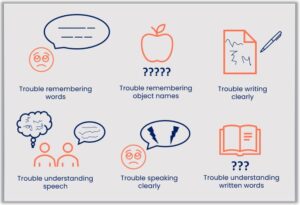

Aphasia happens when the part of the brain that controls language gets hurt.

A person with aphasia may have a hard time understanding, speaking, reading or writing.

Aphasia does not change intelligence.

There are 2 types of aphasia:

- Expressive – having a hard time producing words or saying what they’re thinking

- Receptive – having a hard time understanding what they hear or read

Aphasia can change someone’s independence, and learning which can be frustrating. Some things may be hard to do, such as:

- Talking with family and friends

- Telling people about their thoughts and feelings

- Understanding what is said and following instructions

- Remembering what was said

- Finding the right words

- Concentrating when someone is talking

- Being able to write or talk

- Understanding jokes

- Feel alone, frustrated or not as confident

There are a few different types of aphasia, each with their own unique challenges. Here are a few of them:

- Non-fluent Aphasia People with this type know what they want to say but can’t get the words out smoothly. They might speak in short phrases, kind of like texting shorthand — ‘Want water’ instead of ‘I would like a glass of water.’ Reading and writing could be a bit hard too. They can still understand others, though!

- Fluent Aphasia This type is a little different. People with Wernicke’s aphasia can talk easily, but sometimes the words don’t make much sense. It’s like saying ‘couch on the moon’ when they mean ‘let’s go sit outside.’ Understanding others can be tough for them, too and reading and writing might be tricky.

- Global Aphasia This one is more severe. People with global aphasia have lots of trouble with speaking, understanding language and reading and writing. But with support, they can still connect with others through gestures, expressions, and patience.

There are a few different ways aphasia can change communication. Let’s break them down.

Speaking

Some people might know exactly what they want to say but can’t get the words out. It’s like when you have a word ‘on the tip of your tongue’ – only, this happens way more often and can be way harder. Sometimes people might say a different word than the one they meant to say or say the word with the wrong sounds in it.

Understanding Language

People with a brain injury might struggle to understand what others are saying. They might hear the words but have a hard time putting together what they mean, almost like someone is speaking in a foreign language they don’t know.

Reading and Writing

Aphasia can also affect reading and writing. So, reading a text message or even writing a note can be challenging. It’s like all of a sudden letters and words don’t make sense when you read them, or they come out wrong when you try to write them.

Aphasia happens when areas of the brain that control language get damaged. There are a couple of main areas in the brain – one helps us form words and sentences, and the other helps us understand them. If one of these areas or the connections between them gets injured, it can make communication really tough.

But remember, aphasia is different for everyone. Some people have trouble with just speaking, others with understanding, and some with both. It can be mild and hardly noticeable or severe resulting in the person not being able to communicate out loud at all.